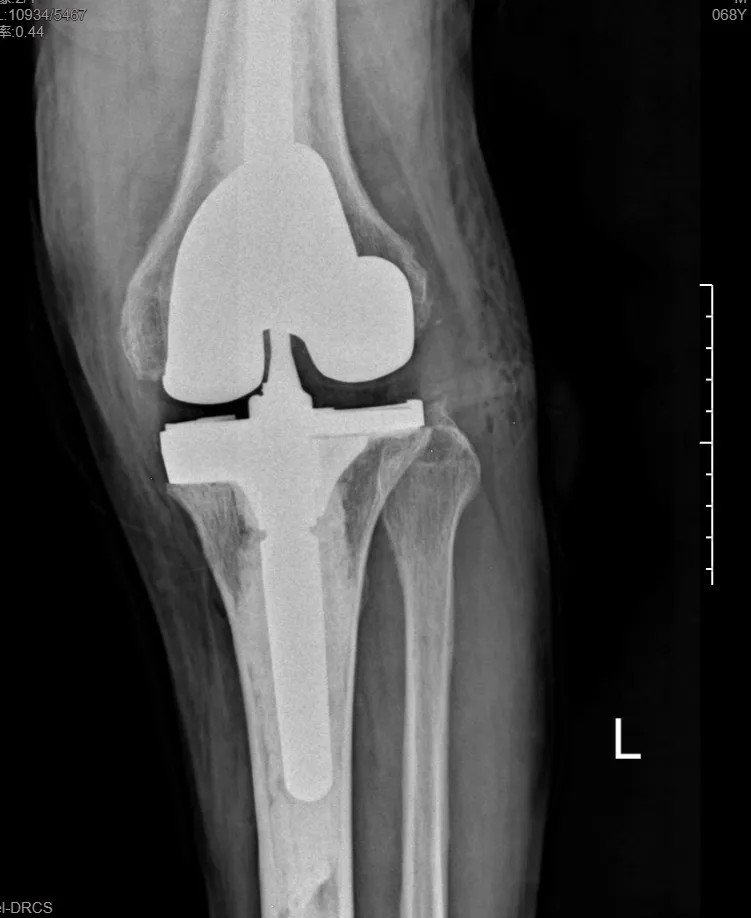

本次手术的核心,是采用了Evolution® ECCK膝关节翻修系统。该系统专为应对翻修手术中常见的严重骨缺损、韧带功能不全等极端复杂情况而设计。

其模块化的组件提供了前所未有的灵活性,就像一套高精度的“工程套件”,允许医生在术中根据实际骨缺损情况,自由组合不同尺寸的垫块、延长杆等部件,实现关节线和力学稳定性的个体化重建。

尤为重要的是,该系统保留了内轴型假体的设计哲学,在重建关节稳定性的同时,努力模仿了人体膝关节自然的运动方式(内轴稳定性、外侧活动性),旨在让患者术后不仅能走,还能走得更舒适、更自然。

集多项前沿科技于一体的精准手术,带来了令人欣喜的结果。术后第一天,在医生指导下,张先生便能够借助助行器下地站立、迈步行走。